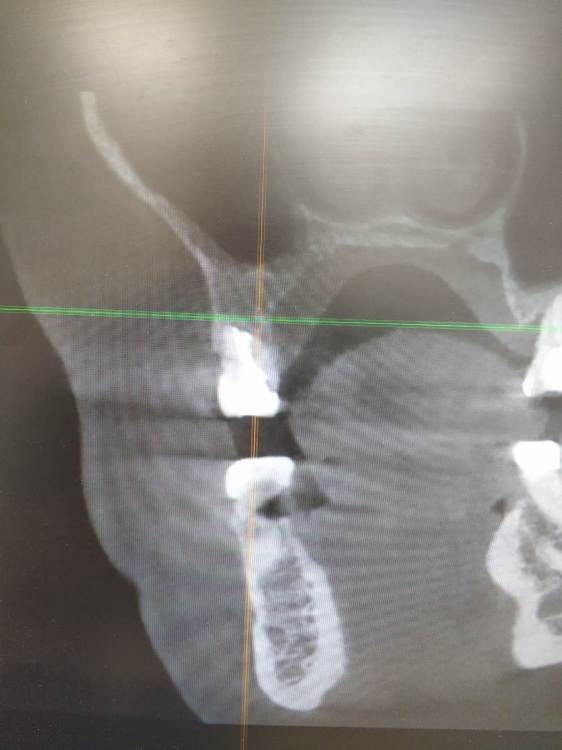

TIGER Опубликовано 29 июля, 2023 Поделиться Опубликовано 29 июля, 2023 (изменено) MAH02590.MP4 Всем привет!Последние лет 5 с внедрением микроскопа в практику стало больше зубо-сохранения,меньше болтов соответственно,что меня радует)Пациент направлен коллегой ввиду невозможности ортоградной ревизии.Проведена зубосохраняющая операция,зуб сохранён.симптомов нет)видео ретро препа тут https://youtu.be/3ukPvjdicW8 MAH02590.MP4 Изменено 29 июля, 2023 пользователем TIGER 3 1 Ссылка на комментарий

Fin Опубликовано 29 июля, 2023 Поделиться Опубликовано 29 июля, 2023 (изменено) Благодарю за кейс.Спрошу пару стандартных вопросов).Чем пломбировали канал? Чем останавливали кровотечение? До ретроградной пломбировки пол зуба уже было не в кости, не будет ли подвижности зуба после все таки 1 треть останется в костной ткани. Изменено 29 июля, 2023 пользователем Fin Ссылка на комментарий

TIGER Опубликовано 29 июля, 2023 Автор Поделиться Опубликовано 29 июля, 2023 @Fin спасибо!Канал пломбирую IRM,гемостаз применение артикаина 1:100,капрамин,кости там норм,подвижности нет,плюс сохранения зуба,что организм нам союзник,в отличие от импланта) 1 Ссылка на комментарий